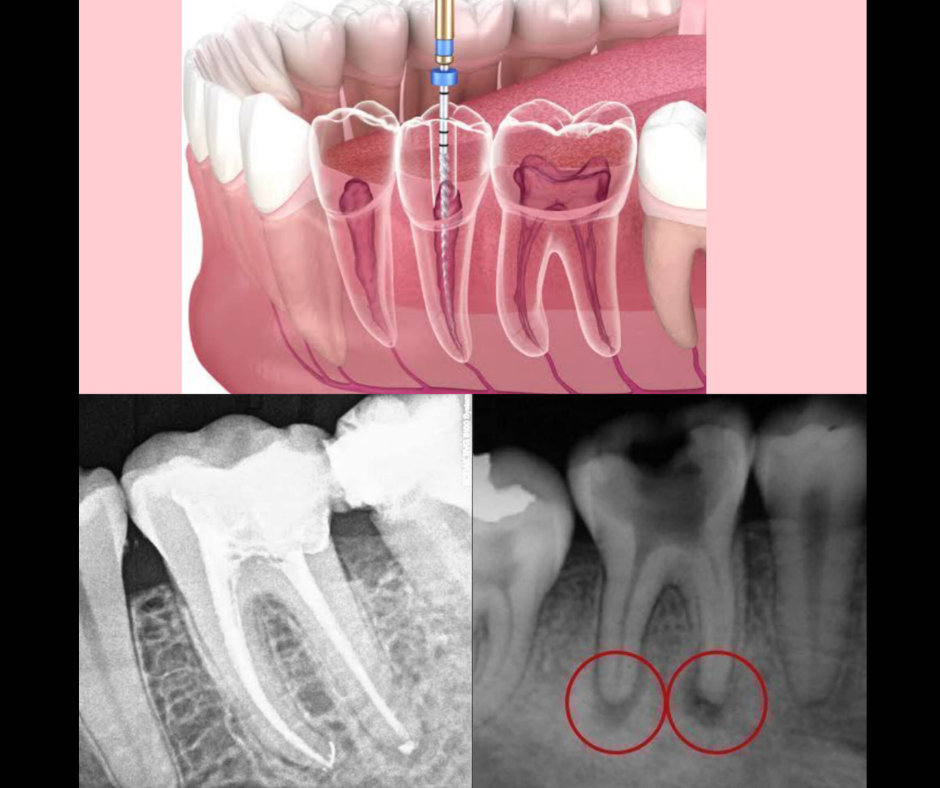

La endodoncia —conocida como “tratamiento de conducto”— es un procedimiento que permite salvar un diente afectado por infección, dolor o daño profundo.

En lugar de extraerlo, lo preservamos para que sigas usando tu diente natural.

¿Por qué elegir la endodoncia?

Porque mantiene tu propio diente. Eso significa:

Evitas la extracción